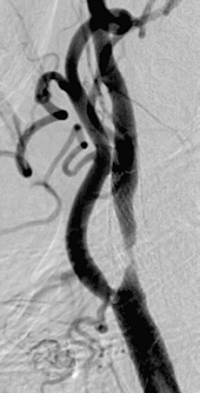

Retromboza smanjuje šansu za ponovnu revaskularizaciju. Mogućnosti za korekciju retromboziranog segmenta se moraju pre reoperacije proceniti kontrolnom arteriografijom.

Karotidna angioplastika je prvi izbor lečenja karotidne restenoze. Međutim, u slučaju tortuoziteta supaaortičnih grana, kalcifikacija i veoma dugačkih lezija endovaskularni tretman može ostati bez uspeha, pa je indikovano ponovno hirurško lečenje.

Multislajs CT angiografija supraaortičnih grana – restenoza zajedničke i unutrašnje karotidne arterije (desno) nakon standardne endarterektomije,

posle 19 godina.